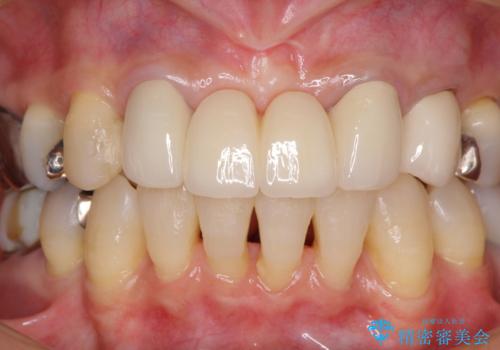

仮歯自体はとても綺麗でしたが、2本の歯が欠損している部分に上唇小帯が入り込んでいたため、歯肉形成を行った上で仮歯を調整し、オールセラミックブリッジを装着することとしました。

他にも治療が必要な歯があったため、合わせてセラミッククラウンやセラミックインレーで治療することとしました。

上唇小帯を切除したことで、ブリッジのダミー部分に触れて腫れていた歯肉は健全な状態になりました。

隙間もなくなったことで話す際の空気の漏れや、ものが挟まることもなくなりました。